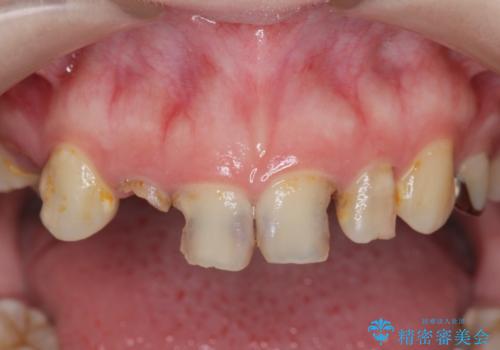

- 放置した虫歯の歯がボロボロになってしまい治療を希望され来院されました。

残根状態の歯、神経まで虫歯が達し失活した歯、歯肉縁下まで及んだ虫歯が多数認められます。